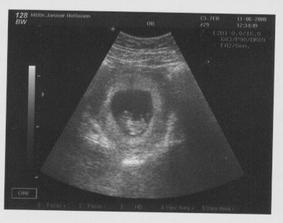

11.6.2008 první UTZ, přes všechen strach, mimísek je tam, je asi 10 tt + 0 a srdíčko mu bije jako zvon, dokonce mi i mávalo, byl to úžasný zážitek